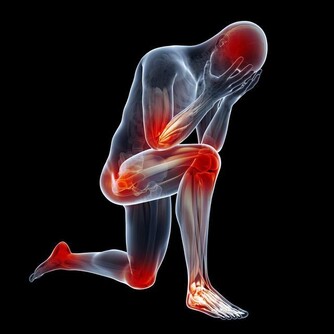

*****2、容易出現頸椎疾病*****

說到低頭族相信大家都能想出是什麼,歸根結底它就是指人們低著頭玩手機的現象,如果說一天24小時,那麼幾乎三分之一的時間都在玩手機,但是人們卻不知道我們在玩手機的同時自己是得到了滿足,但是自己的身體卻越來越下降,特別是自己的頸椎,長時間低著頭就會使得頸椎的神經得到壓迫,不利於其血液的流通,所以說經常玩手機的人很容易出現頸椎病。